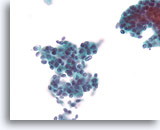

Lobulair neoplasie, Borst FNA, Celblok.

Een in-situ groeipatroon van lobulaire neoplasie is moeilijk of onmogelijk te identificeren in cytologische preparaten. Deze cluster van ongeveer 5 trossen is gedeeltelijk opgezet door het kenmerkende patroon van een losse ‘zak knikkers’ van lobulaire neoplasie zonder vorming van een glandulair lumen.

Lobulair neoplasie, Borst FNA, Celblok.

Een in-situ groeipatroon van lobulaire neoplasie is moeilijk of onmogelijk te identificeren in cytologische preparaten. Deze cluster van ongeveer 5 trossen is gedeeltelijk opgezet door het kenmerkende patroon van een losse ‘zak knikkers’ van lobulaire neoplasie zonder vorming van een glandulair lumen.

Lobulair neoplasie, Borst FNA, Celblok.

Een sterkere vergroting toont een kenmerkende targetoïde cytoplasmische vacuole (pijl)

Lobulair neoplasie, Borst FNA, Celblok.

Een sterkere vergroting toont een kenmerkende targetoïde cytoplasmische vacuole (pijl)